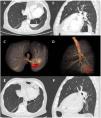

Multiplanar chest CT reconstructions with intravenous contrast in axial (A) and sagittal (B) planes where a bulla located in the medial basal segment of the LLL with hematic level is observed. 3D segmentation of the findings in axial (C) and sagittal (D) projection. In orange (C and D), the airway and bulla stand out, and bleeding is shown in red. Multiplanar CT reconstructions without intravenous contrast in axial (E) and sagittal (F) planes 5 months later. Persistence of the bulla located in the medial basal segment of LLL with smaller size and in the absence of the hematic level (E and F).

A 70-year-old man, ex-smoker, diagnosed with atrial fibrillation anticoagulated with acenocoumarol, who also suffered from severe COPD, was admitted to the hospital due to a 2-day history of hemoptysis (20 cc per day). A chest computed tomography (CT) scan revealed emphysema regions, along with a bulla in the medial basal segment of the left lower lobe (LLL), with blood content inside (Fig. 1 and Video). Anticoagulation was suspended and a bronchoscopy was performed, which found a possible beginning point, and ruled out the presence of active bleeding. Given the persistence of hemoptysis, a lobectomy or arterial embolization was considered, but due to the hemodynamic stability of the patient, conservative treatment was continued. Finally, the hemoptysis stopped and anticoagulation was restarted. Five months later, bulla reduced and had no hematic level. The patient was totally asymptomatic.